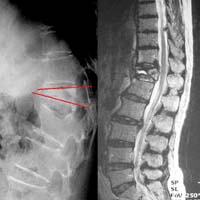

<¸ñµð½ºÅ©>

<¼ö¼úÀü>

<¼ö¼úÈÄ>

¾çÃø

»óÁö ÅëÁõÀ» ÁÖ¼Ò·Î ³»¿øÇÑ È¯ÀÚÀÇ °æÃߺÎ

MRI¼Ò°ß, ¼ö¼úÈÄ ¼Ò°ß

<Ç㸮µð½ºÅ©>

Á¦

4.5¹ø ¿äÃߺΠÃß°£ÆÇ Å»ÃâÁõÀ¸·Î ¼ö¼úÇÑ

ȯÀÚÀÇ ¿äÃß MRI¼Ò°ßÀ¸·Î ¼ö¼úÈÄ Å»Ãâ

µð½ºÅ©ÀÇ Á¦°ÅµÈ ¸ð½À°ú ÀûÃâµÈ µð½ºÅ©¸¦

º¼ ¼ö ÀÖ´Ù.

<ôÃß°ÇùÂøÁõ>

ÇÏÁö ¹æ»çÅë°ú °£ÇæÀû ÆÄÇàÀ» ÁÖ¼Ò·Î ³»¿øÇÑ

ȯÀÚÀÇ ¿äÃߺΠMRI ¼Ò°ßÀ¸·Î ôÃß°ü ÇùÂøÀ¸·Î

ÀÎÇØ ô¼ö½Å°æÀÌ ¾Ð¹Ú ¹Þ´Â ¼Ò°ßÀ» º¼

¼ö ÀÖ´Ù.

<ôÃßÀü¹æÀüÀ§Áõ>

ÇÏÁö ¹æ»çÅëÀ» ÁÖ¼Ò·Î ¼ö¼ú ½ÃÇàÇÑ ¸ð½ÀÀ¸·Î

Ãß°æ ³ª»ç¸ø°íÁ¤¼ú ¹× Ãß°£À¶ÇÕ¼ú½ÃÇà·Ê